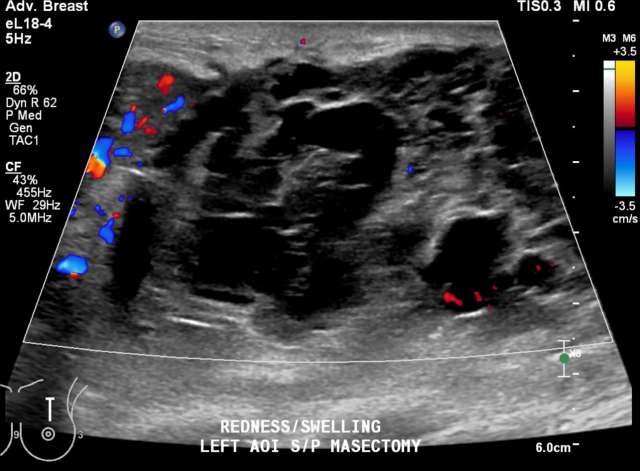

• US: Heterogenous fluid collection with fluid-fluid level, Figure 2.

Case: Post-Surgical Fluid Collections Figure 2

Figure 2 - Ultrasound demonstrating post-surgical hematoma of the right breast. Heterogenous fluid collection with fluid-fluid level (yellow arrow). There was ecchymosis overlying the area of interest in the upper inner quadrant.